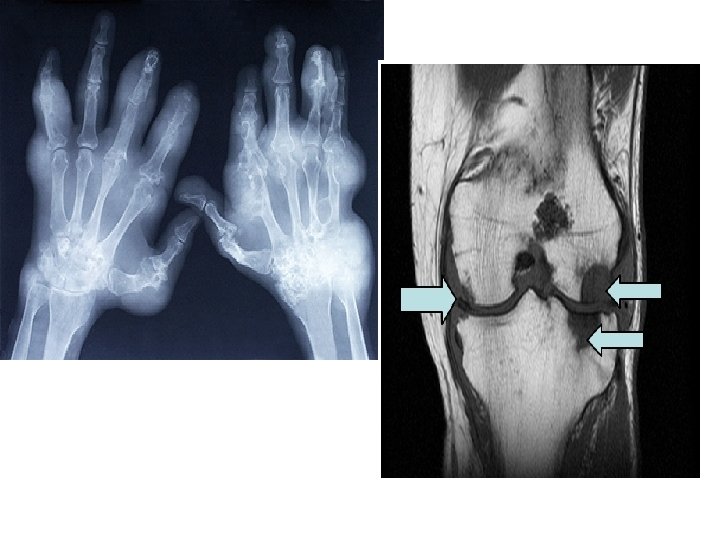

Arthritis

Gout • Gout is a disease that results from an overload of uric acid in the body. This overload of uric acid leads to the formation of tiny crystals of urate that deposit in tissues of the body, especially the joints. When crystals form in the joints it causes recurring attacks of joint inflammation (arthritis). Chronic gout can also lead to deposits of hard lumps of uric acid in and around the joints and may cause joint destruction, decreased kidney function, and kidney stones.

Joints A joint, or articulation, is the place where two bones come together. • Fibrous- Immovable: connect bones, no movement. (skull and pelvis). • Cartilaginous- slightly movable, bones are attached by cartilage, a little movement (spine or ribs). • Synovial- freely movable, much more movement than cartilaginous joints. Cavities between bones are filled with synovial fluid. This fluid helps lubricate and protect the bones.